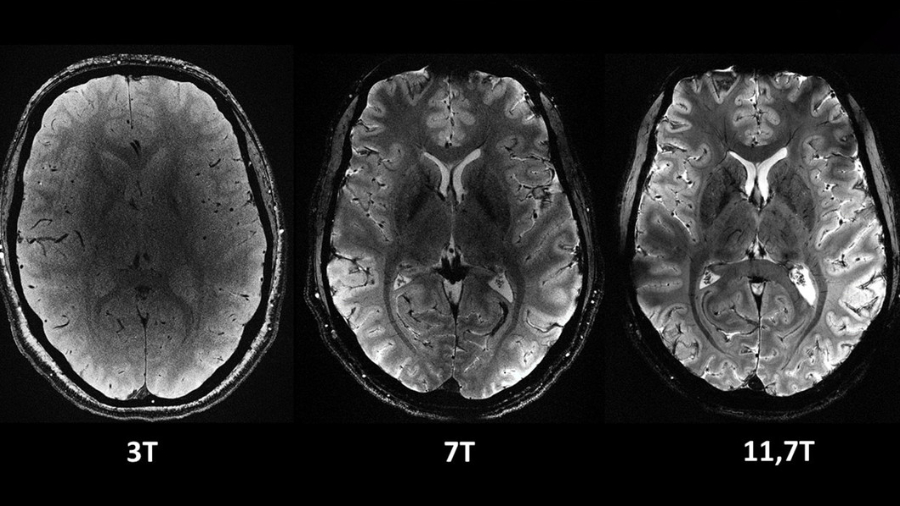

La resonancia magnética más potente del mundo muestra sus primeras imágenes

En un estreno mundial, los investigadores de la Comisión de Energía Atómica (CEA) de Francia revelaron este martes una serie de imágenes 'in vivo'...